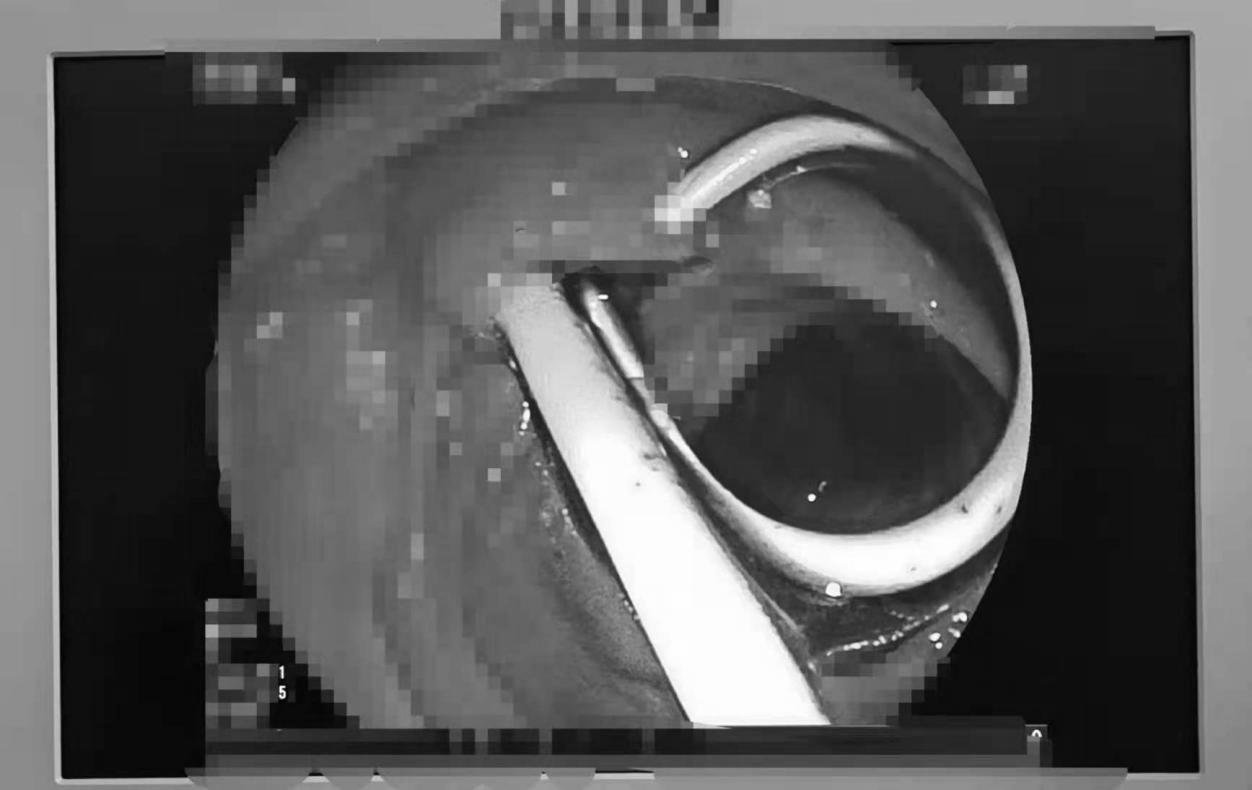

手术过程中,章诺贝教授在经内镜下对胰管插管造影后发现胰管起始部见数个大小不等的充盈缺损影,最大者为23mm*15mm。胰管内的巨大结石,这无疑为手术加大了难度。紧急情况下,手术团队决定施行乳头小切开,经反复对胰管进行扩张后,顺利越过梗阻部位至远端胰管并置入胰管支架,胰液引流通畅并见较多蛋白栓子随胰液流出,同时在胆管置入胆管支架,大量墨绿色胆汁通过胆道支架流出,手术十分成功,术后患者恢复良好。

ERCP的中文名称叫内镜下逆行胰胆管造影,是通过十二指肠镜进入十二指肠,找到十二指肠乳头,也就是胆管和胰管排泄胆汁和胰液的开口处,然后进行插管。造影可使胆管和胰管在X线下显影,从而检查胆管或者胰管内的病变。起先是一种检查手段,但随着技术的逐步成熟,现在已经被广泛应用于检查和治疗胆胰疾病,如胆总管结石、胰管结石或者胆道梗阻,包括各种原因引起的胆道梗阻需要引流的患者。